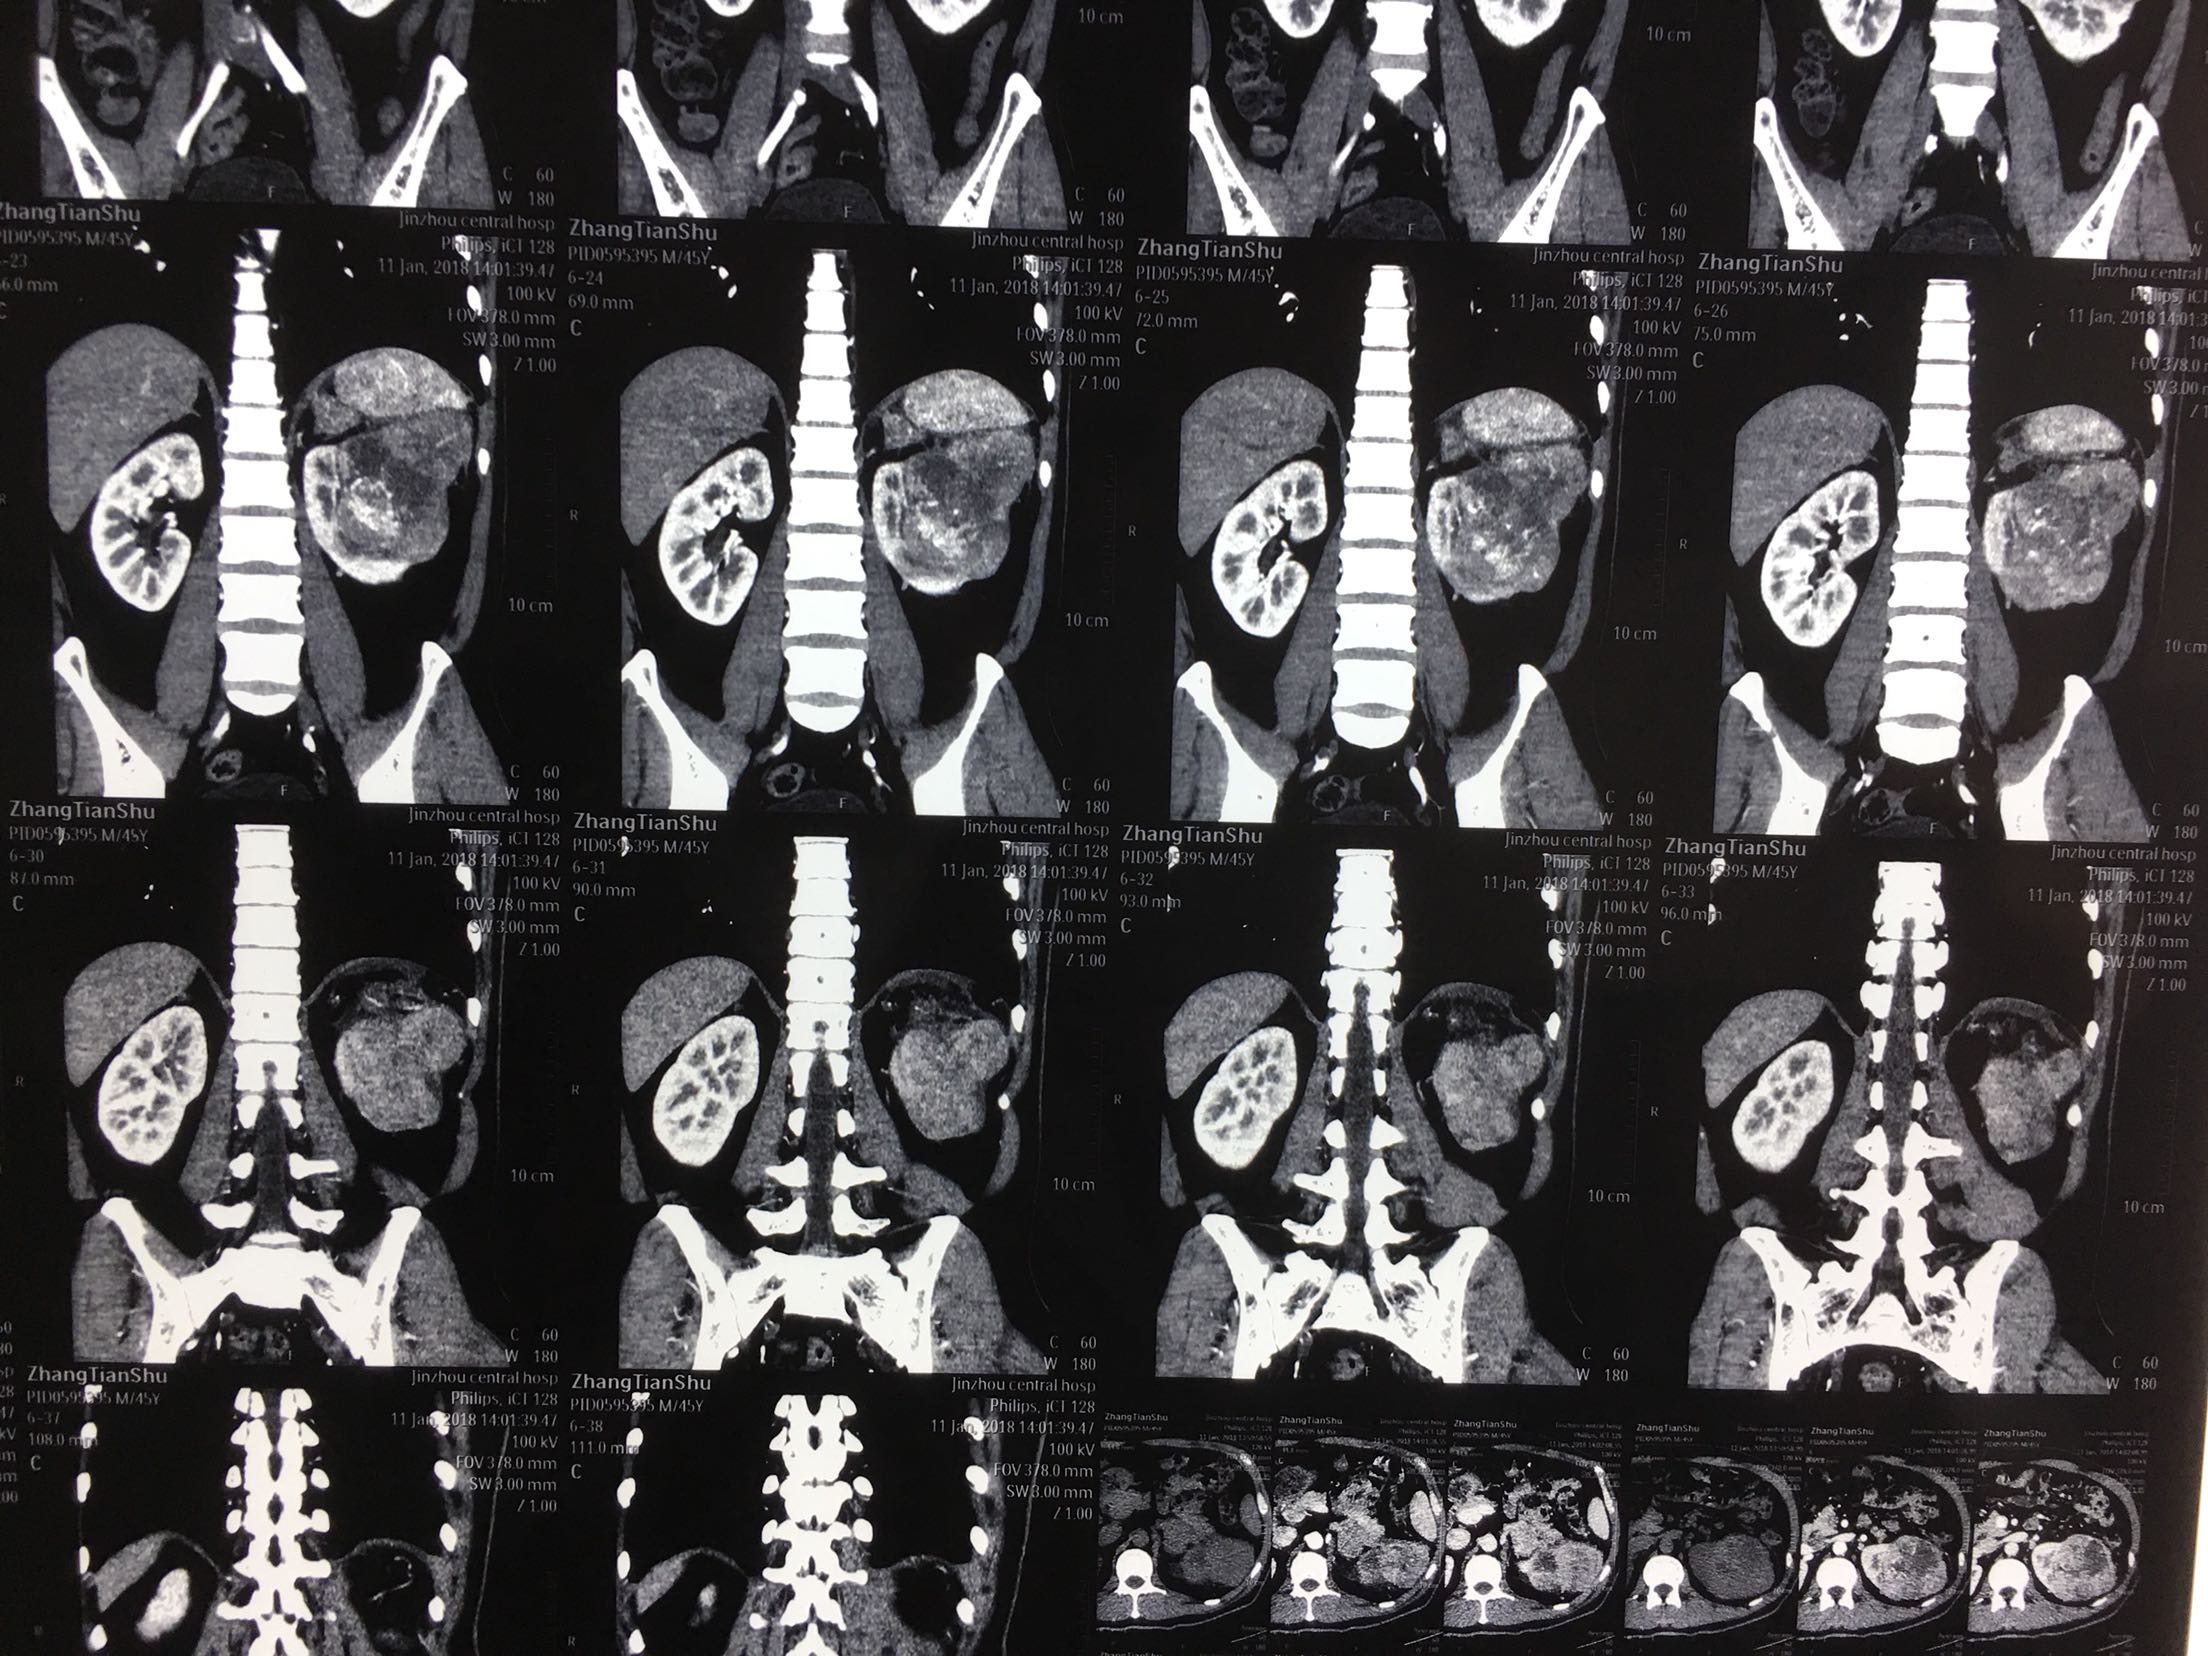

查体:左肾区轻叩击痛,双输尿管走形区无压痛,耻骨上区无隆起及压痛, 辅助检查:泌尿系彩超:左肾肿瘤。 ctu:左肾癌伴同侧肾上腺侵犯。

诊断:左肾癌伴肾上腺转移 治疗:根治性左肾切除术

术后病理:左肾透明细胞癌局部肉瘤样变,肾上腺及腹膜累及。 讨论:肾脏肿瘤肉眼血尿,腰疼,腹部包块为晚期肿瘤症状,预后不良。